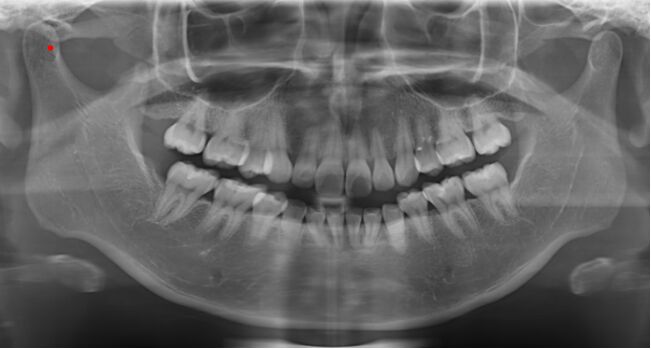

79.所附X光片右側髁頭(condyle)上之紅色圓點標示處,最可能的解剖位置為下列何者?(A)髁頭的內側 (B)髁頭的外側 (C)髁頭的前側 (D)髁頭的後側